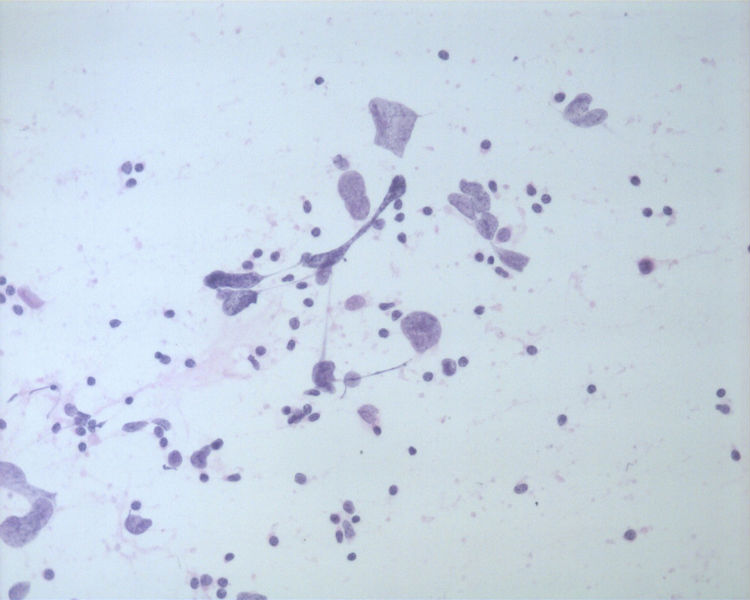

• 男性,50岁,右锁骨上淋巴结穿刺。图1

图1

• 男性,50岁,右锁骨上淋巴结穿刺。图2

图2

• 男性,50岁,右锁骨上淋巴结穿刺。图3

图3

基本都是淋巴细胞背景中散在异形非常明显的细胞。细胞无成巢现象。

这是一例我以前穿刺的病例。当时涂片发现淋巴细胞的背景中散在大而非常异形的细胞。细胞没有成巢现象。